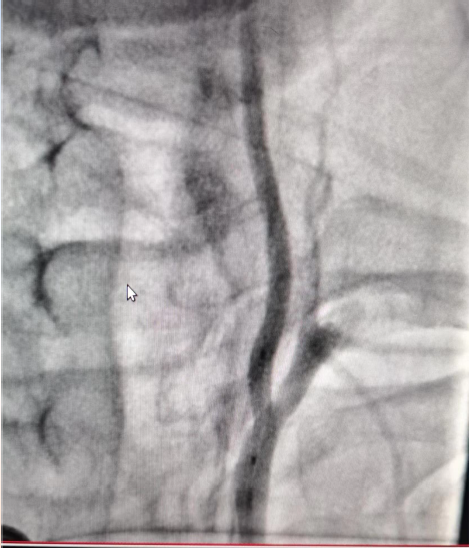

初始造影RICA起始位

病历夹什么径技·第152期|串联营病历夹:川陕大营_https://www.jmylbn.com_新闻资讯_第81张

初始造影后循环+LICA正位

病历夹什么径技·第152期|串联营病历夹:川陕大营_https://www.jmylbn.com_新闻资讯_第82张

手术过程

在Synchro微导丝与Rebar-18支架导管的辅助下顺利超选上去,借助Transend导丝使用球囊穿梭技术将Sprinter(3*15)球囊装入血管真腔中。

过程影像

病历夹什么径技·第152期|串联营病历夹:川陕大营_https://www.jmylbn.com_新闻资讯_第83张

病历夹什么径技·第152期|串联营病历夹:川陕大营_https://www.jmylbn.com_新闻资讯_第84张

<<滑动查看下一张图片>>

由于guiding通过失败所以先处理近端,将Spider FX(5)保护伞置入进行了远端保护,近端放置了WALLSTENT支架,然后收伞,顺势将guider通过,结果其无法到达远端。

病历夹什么径技·第152期|串联营病历夹:川陕大营_https://www.jmylbn.com_新闻资讯_第85张

病历夹什么径技·第152期|串联营病历夹:川陕大营_https://www.jmylbn.com_新闻资讯_第86张

狭窄段用四个球囊后扩张,将cat6推过狭窄段,发现可能存在远端栓塞,因此将guider退了一下。

病历夹什么径技·第152期|串联营病历夹:川陕大营_https://www.jmylbn.com_新闻资讯_第87张

对侧造影显示,右侧大脑前动脉供血区血流较好。

病历夹什么径技·第152期|串联营病历夹:川陕大营_https://www.jmylbn.com_新闻资讯_第88张

接下来处理远端,Synchro微导丝与Rebar微导管的辅助下,选择置入Solitaire(4-20)支架,支架打开后使用抽拉结合的方式使血管再通。

病历夹什么径技·第152期|串联营病历夹:川陕大营_https://www.jmylbn.com_新闻资讯_第89张

取栓后造影如下: